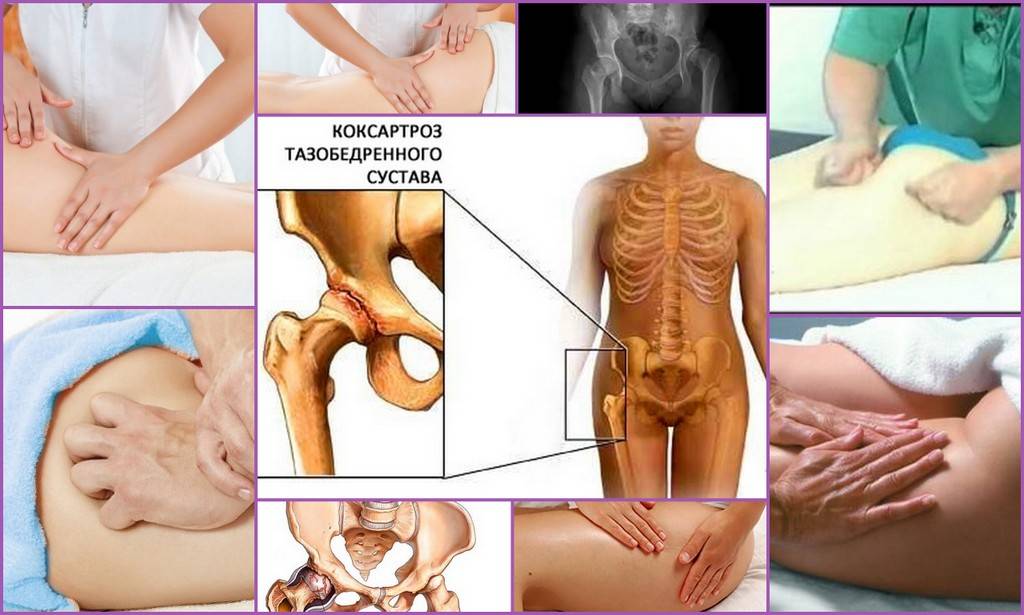

Замена таз сустава

Замена таз сустава 113 фотографий